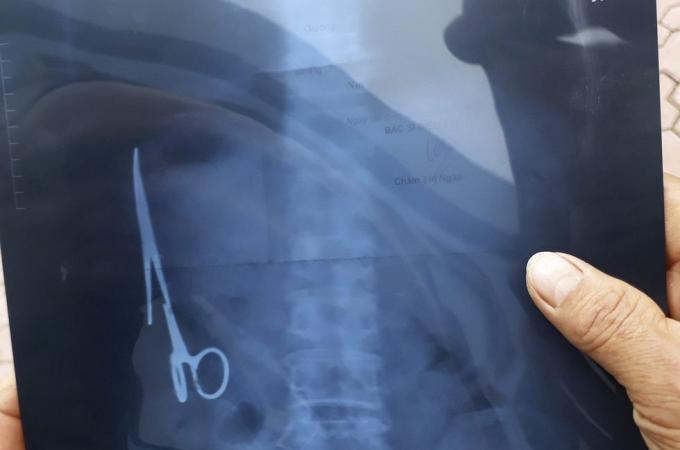

Osmnáct let! Tak dlouho nosil Vietnamec ve svém břiše chirurgické nůžky